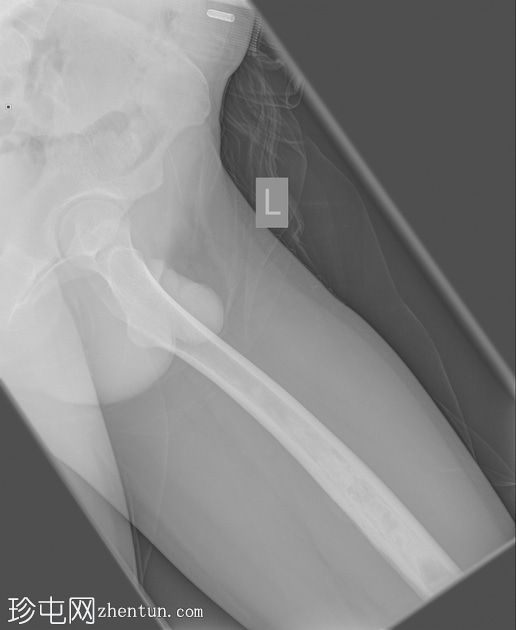

X光片

斜面

左股骨中段可见边界不清的硬化区域,伴有宽阔的过渡区和虫蛀状外观。

邻近软组织可见小块钙化灶。无骨折或脱位。